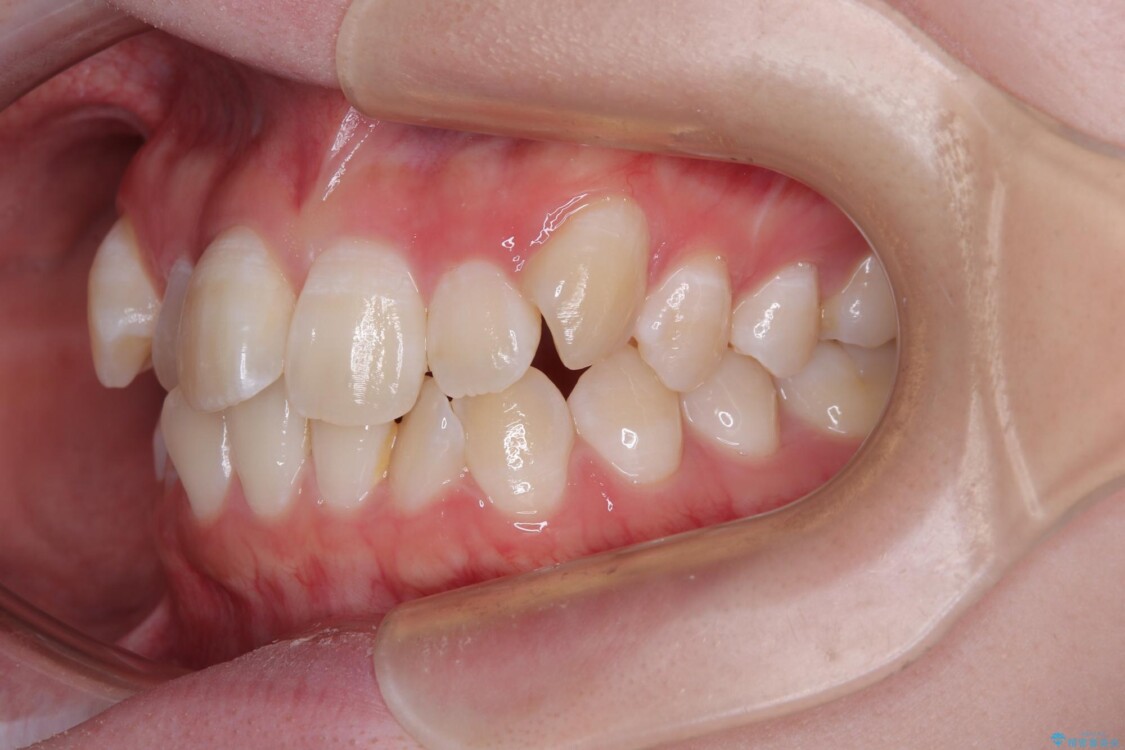

「前歯のデコボコ(叢生)をきれいに整えたい」とのことでご来院されました。

治療前

• 【モニター】前歯のデコボコをスッキリ解消!目立ちにくいワイヤー矯正でスピーディに治療完了 治療前画像